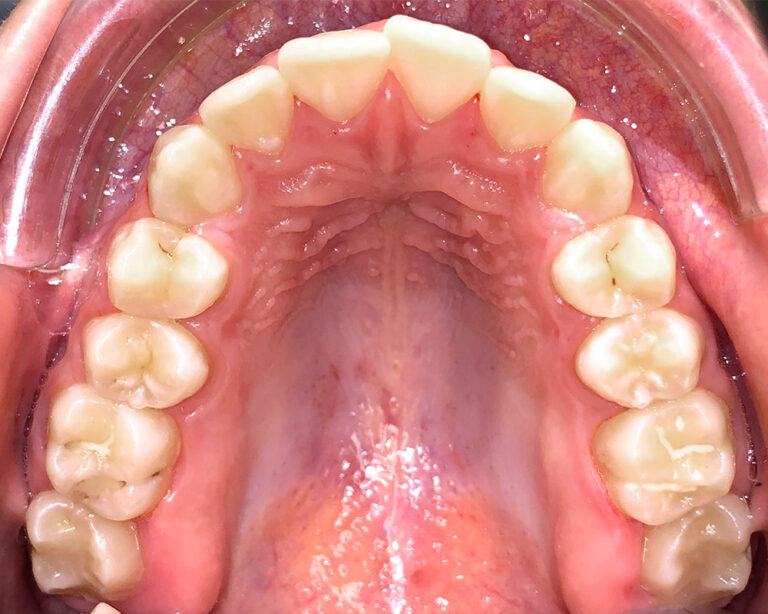

Кейс 16

Акинфиева

Количество кап ВЧ 20

Количество кап НЧ 20

ДО

ПОСЛЕ